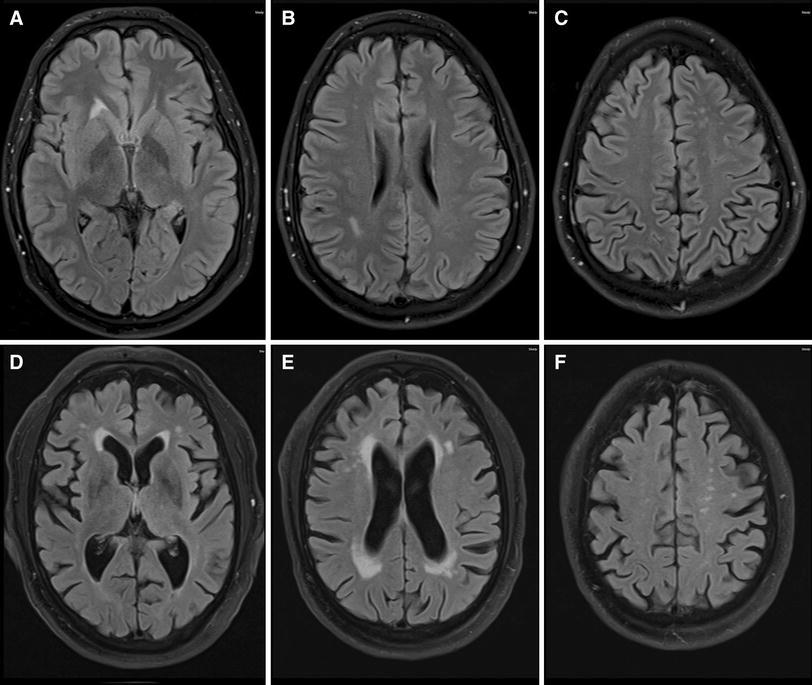

The disease is caused by mutations in the protein tyrosine kinase domain of colony‐stimulating factor 1 receptor (csf1r), encoded by the csf1r gene on chromosome 5q34. Hereditary diffuse leukoencephalopathy with spheroids (hdls) is a rare autosomal dominant disorder characterized by cerebral white matter degeneration with myelin loss and axonal swellings (spheroids) leading to progressive cognitive and motor dysfunction.